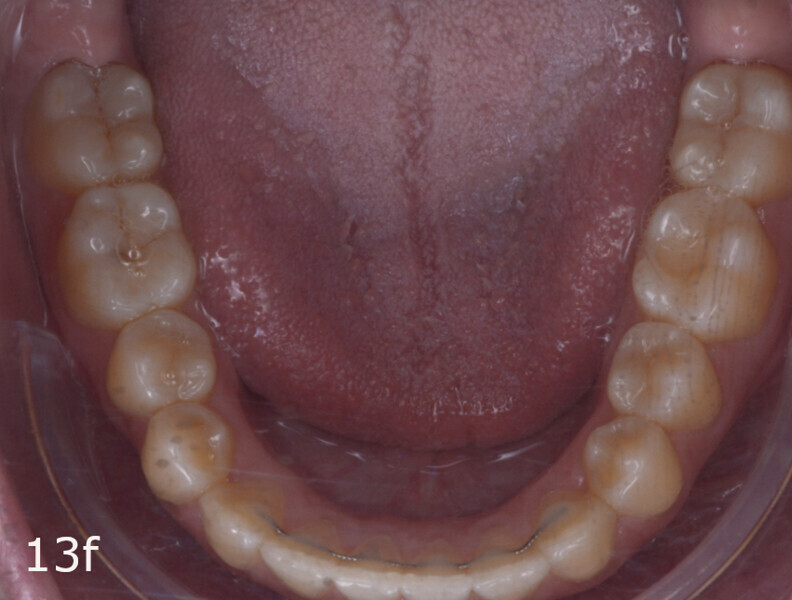

The total treatment time was 15 months. An Angle Class I relationship was established along with adequate anterior and canine guidance, establishing a functional occlusion. This not only ensures optimal masticatory function but also protects the teeth and the temporomandibular joint from excessive force. Maxillary and mandibular fixed retention were installed at the end of the treatment (Figs. 13–19).